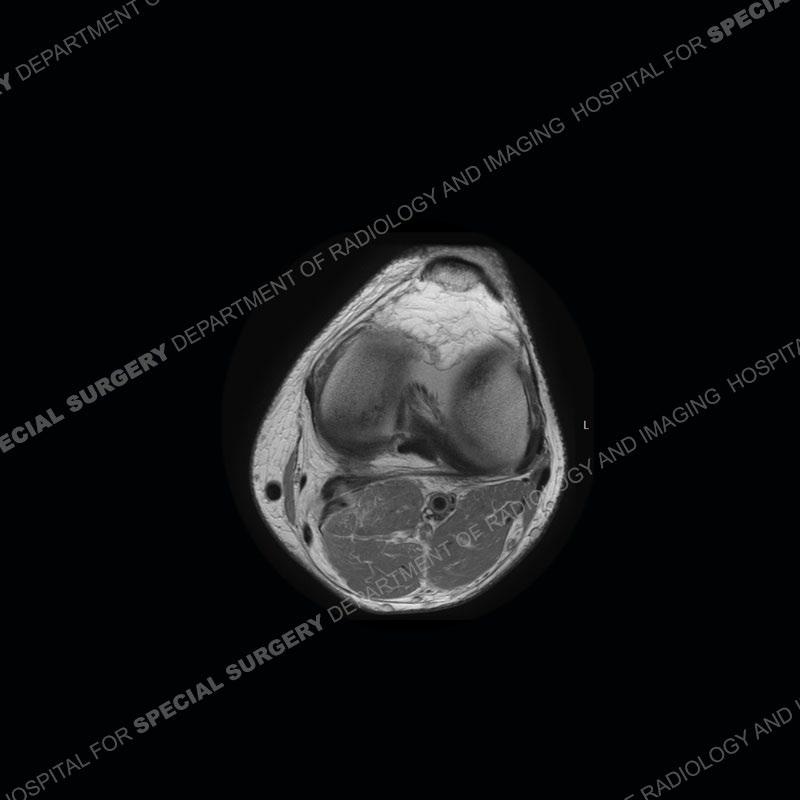

The radiographs show degenerative change of the medial compartment and a varus knee, but they are not germane to this case. No acute bony injury is present. The MRI shows edema of the posterior medial knee/soft tissue and a focal area of a partially disrupted low signal structure. The details are kept at a minimum in the findings of this case on purpose.

Diagnosis: Partial Disruption Medial Head Gastrocnemius (MHG)

Fourth, use all imaging planes and different pulse sequences to make your diagnosis. The edema highlighted in this case can be seen as the obscuration of fat on the PD images but is much easier to perceive as the high signal on the IR pulse sequences. The actual disruption of the MHG myotendinous junction is only able to be seen on the axial images. On the sagittal and coronal images, we get a sense something is wrong but hard to be exact. Lastly, when you look at a study and something just seems off (as I would say the sagittal and coronal images do with that dark band of tissue posteriorly), listen to yourself and go through the study slowly and meticulously. Most of the time you will find you were right, and something indeed is present.